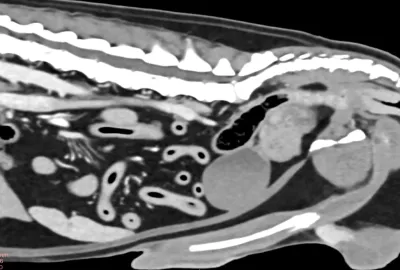

Břicho:

diagnostika nádorových onemocnění, vč. kontroly po jejich léčbě, patologie velkých cév, nemoci jater a žlučových cest, onemocnění ledvin a močopohlavního aparátu. Patologie v oblasti pánevní dutiny - prostata, nádory pánve, fraktury pánve. Diagnostika příčin hromadění tekutiny v břiše – ascitu.